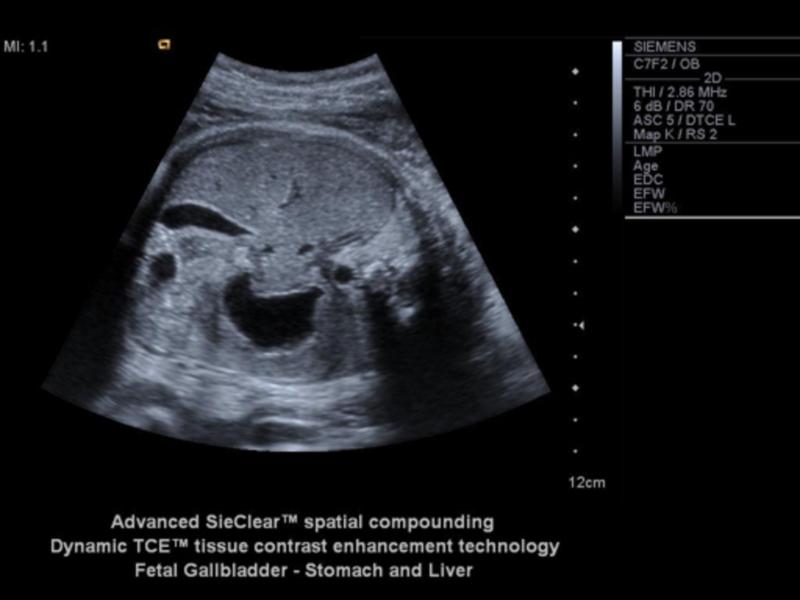

Fetal GB

Fetal GB

Fetal GB

When can the stomach be seen?

14 weeks

If the stomach is not seen by 16 weeks, what could be the problem?

esophageal atresia

What is the stomach a landmark for?

AC